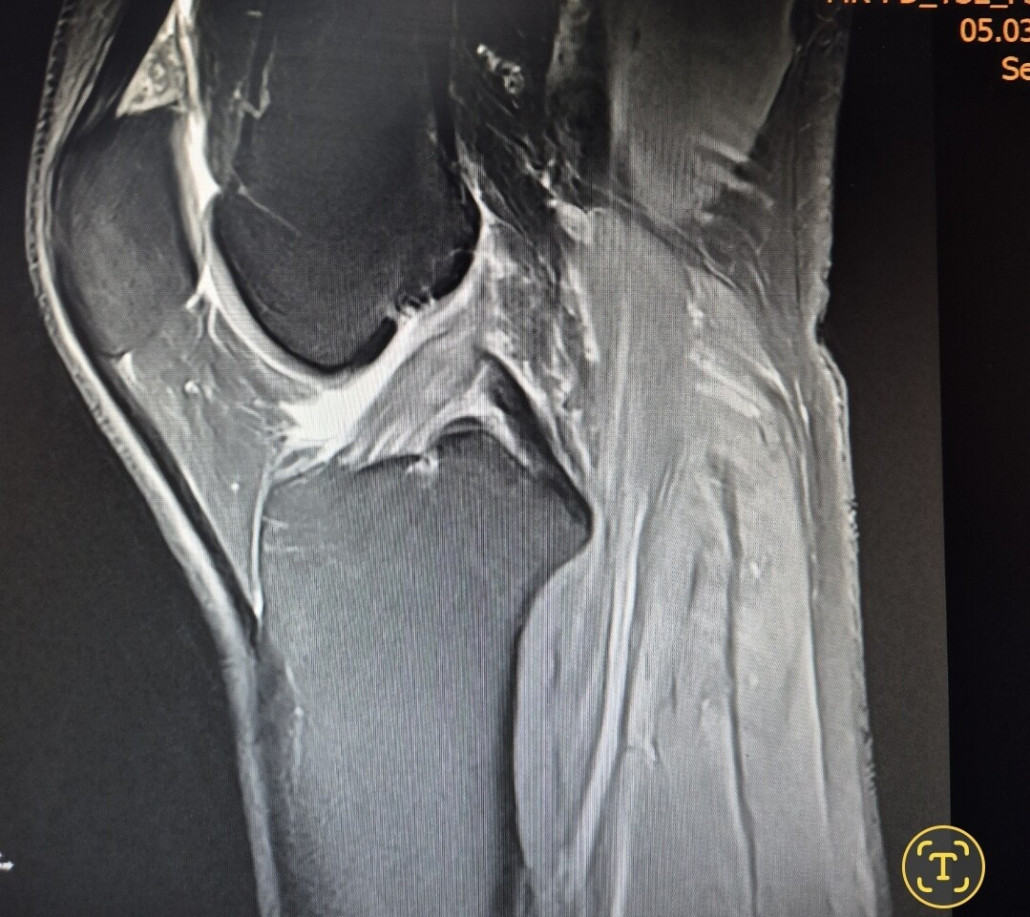

Ich war beim MRT ( Knie verletzt im letzten Skiurlaub), da nach 2 Monaten meine Knieprobleme nicht besser wurden. Ich war neugierig und hab die CD in meinen PC geschoben, hier ein Screenshot von einer Stelle, die glaube ich nicht so gut aussieht....

meinst du das?

Ich bin kein Arzt, also nimm meine Einschätzung bitte nicht als 100 % korrekt oder besser gar nicht Ernst.... Aber ich vermute, dass du ein Problem mit einem Kreuzbandriss hast...

Die Bänder sollten wie dicke, durchgehende schwarze Linien aussehen. Dein PCL scheint in Ordnung zu sein, aber dein ACL sieht nicht so gut aus.

Ich wiederhole: Ich bin kein Arzt, aber so sah das Bild meiner Frau aus, und der Arzt hat es damals bestätigt.

Zunächst fällt auf, dass viel "weiße Masse" auf dem Bild zu erkennen ist - und das an Stellen, wo sie nicht zwangsläufig sein sollte. Das lässt die Vermutung von Flüssigkeitsansammlung und damit Verletzungen innerhalb des Knies zu. Wenn ich das Bild mit jenem einer guten Freundin vergleiche, die sich im Dezember das Vordere Kreuzband gerissen hat, würde ich auch stark auf eine Verletzung des vorderen Kreuzbands tippen. Ob Teil- oder Komplettruptur, dafür reicht mein Laienwissen wahrlich nicht aus.